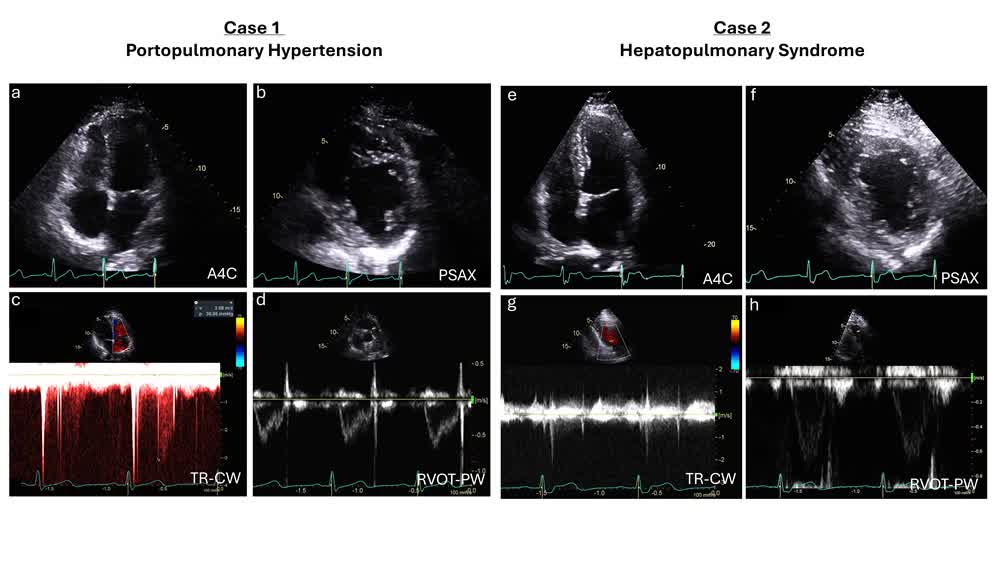

Exercise hemodynamics with bubble injection into the pulmonary artery in evaluation of hepatopulmonary syndrome and portopulmonary hypertension in hypoxemic patients with liver disease Yogesh Reddy @mayoclinicCv Fadi Adel, MD #AHAJournals ahajrnls.org/3G7n1Pd